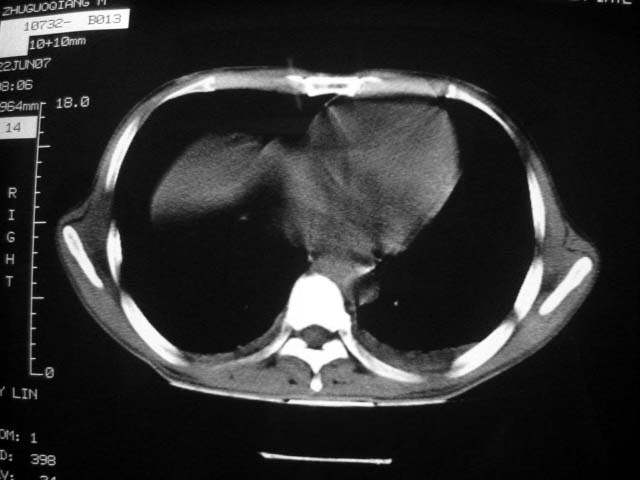

前几次大家认为是转移癌,但此次复查病灶却明显吸收好转,不支持诊断。请大家讨论。[emb10]

患者现无咳嗽咳痰及咳血,肝功好转,血清白蛋白降低,球蛋白升高,白球比小于0.5.少量腹水。

回顾既往片,病变明显吸收,缩小,未经治疗,不支持肺转移瘤,可能为肺结节病或韦格氏肉芽肿

支持韦格氏肉芽肿

患者近期复查胸ct正常,轻度肝功异常,保肝、抗病毒(拉美夫叮)治疗中。